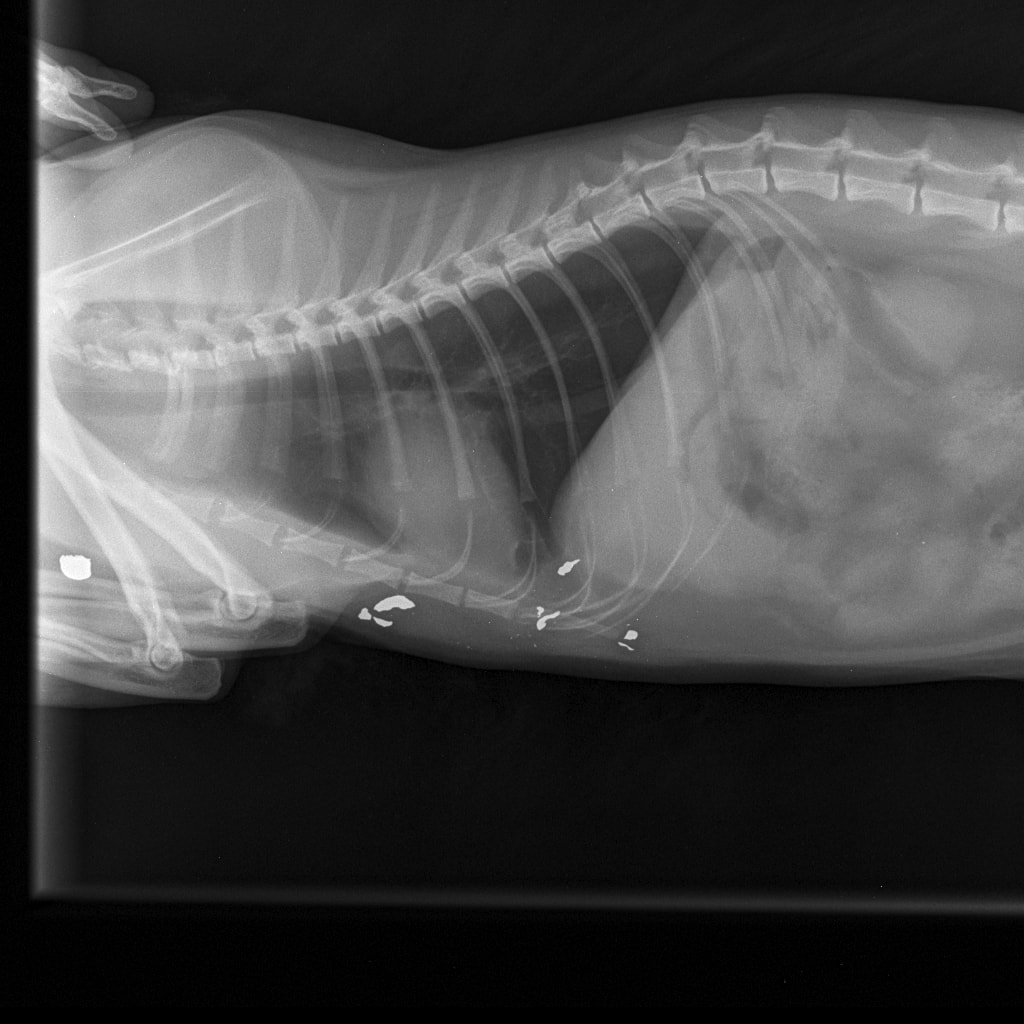

– Nikako ne mogu razumjeti da mi je netko namjerno ubio životinju. I to metkom koji se rasprsnuo u tijelu malene životinje što nije metak iz zračne puške. To se lijepo i vidi na rendgenskoj snimci koju smo obavili u Veterinarskoj ambulanti Majcan. U svakom slučaju, prijavili smo sve policiji koja će, iskreno se nadam, čim prije pronaći krivca – rekla nam je tužna vlasnica ubijene životinje.